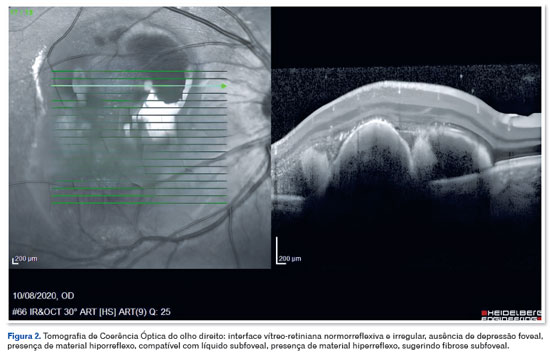

Homem, 39 anos, portador de DM1, diagnosticado na primeira infância por meio de teste PCR com eletroforese capilar e southern blot que identificou repetições patológicas da trinca CTG no gene DMPK, relatou perda de visão recente no OD. Ao exame oftalmológico, a acuidade visual (AV) era 20/100 em OD e 20/20 em OE, ambas com correção. A biomicroscopia revelou conjuntiva clara, córnea transparente, ausência de reação na câmara anterior e cristalino transparente em ambos os olhos. Movimento ocular extrínseco preservado em ambos os olhos. O mapeamento da retina evidenciou hemorragia sub-retiniana em área macular, associada a exsudação em olho direito (Figura 1). O paciente não apresentava alterações retinianas no olho esquerdo. A angiografia fluoresceínica incluiu alguns achados como hipofluorescência por bloqueio na área macular do olho direito. O exame de tomografia de coerência óptica (OCT) evidenciou interface vítreo-retiniana normorreflexiva e irregular, ausência de depressão foveal, presença de material hiporrefletivo, compatível com líquido subfoveal e presença de material hiperreflexivo, sugerindo fibrose subfoveal (Figura 2).